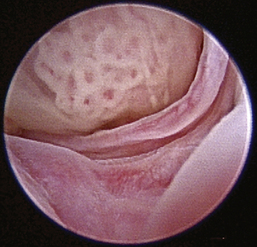

Normal turbinates have a smooth, pink-to-white surface and a spatial alignment that provides channels for the passage of air. The color varies and appears tan in the caudal nasal cavity. Turbinates come in different shapes and sizes, but the surface should be smooth. Ethmoid turbinates in the caudal nasal cavity will have a characteristic stippled or corrugated appearance (Figures 19-13 through 19-16). Ulcerations or various proliferations of the mucosa are indicative of disease. These changes are typically diffuse and accompanied by a lot of mucus. Mucus can be thin to purulent. Copious amounts can be flushed out of the nasal cavity to allow better visibility. The specific disease is determined by biopsy. After full examination of the nasal cavity, run the scope along the floor of the nasal sinus to the level of the choanae. Keeping the scope pointed in a ventral medial direction prevents inadvertent trauma or penetration of the cribriform plate. The index finger of the free hand can be used to follow the scope as it moves caudally over the hard palate; the surgeon can then palpate the scope through the soft palate when it moves into the nasopharynx. Some force is needed to complete this procedure and may result in increased bleeding.

Figure 19-14 Normal canine meatus division.

image